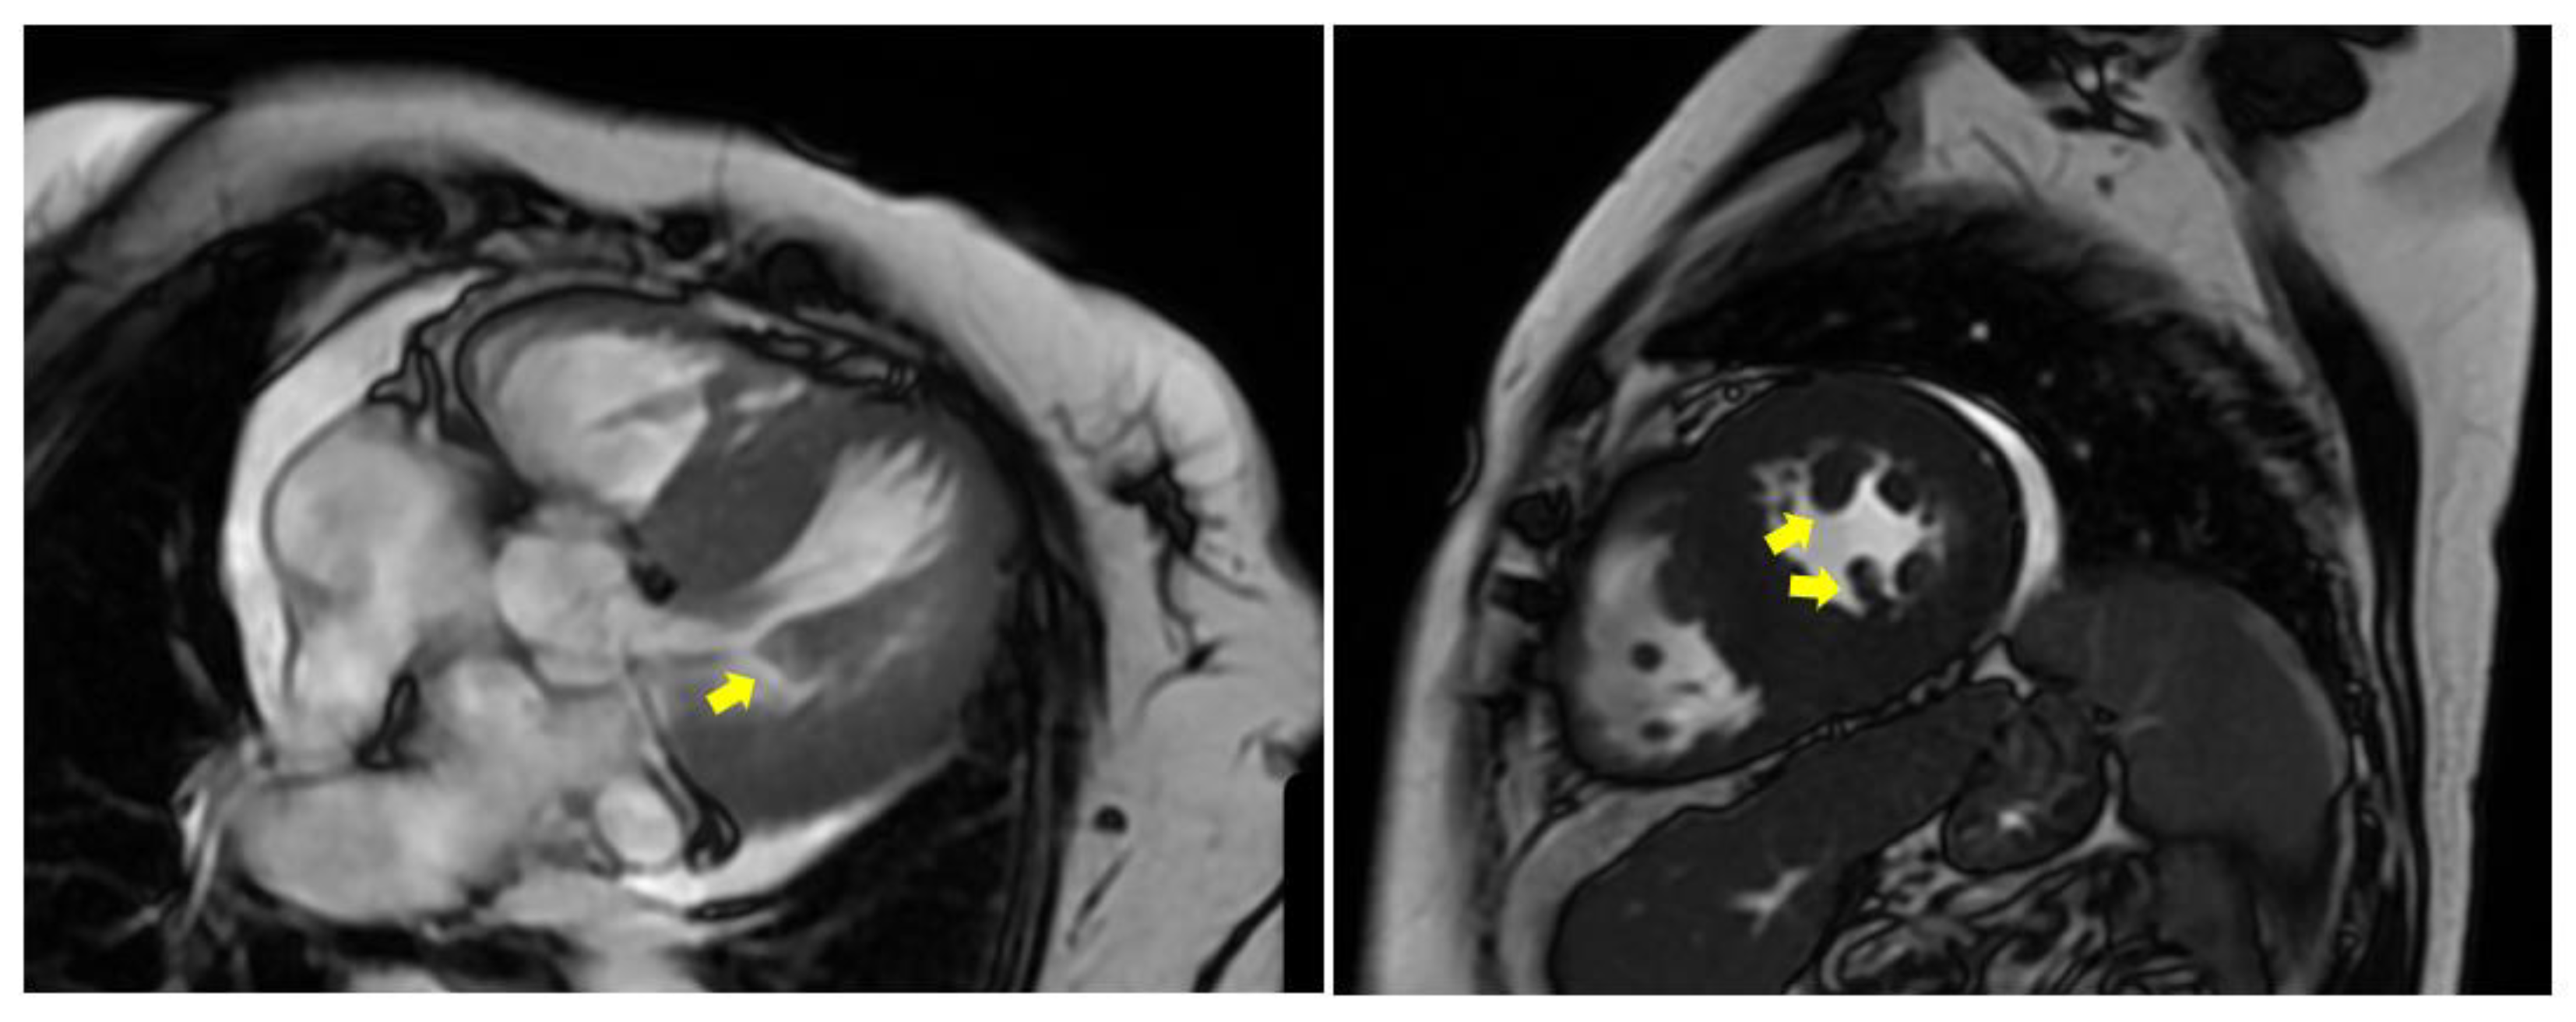

7.2. Hypertrophic (Obstructive) Cardiomyopathy